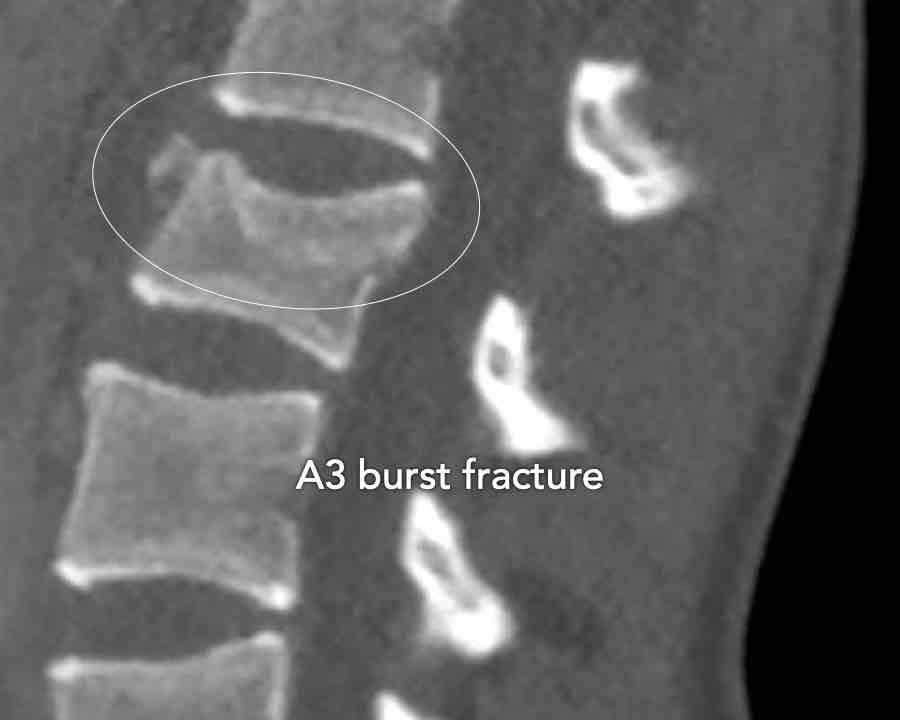

A3 Incomplete Burst fractures

Fracture with any involvement of the posterior wall; only a single endplate fractured.

A vertical fracture of the lamina is usually present and does not constitute a tension band failure.

Findings:

- No C or B injury

- Fractures vertebral body with involvement of upper endplate (1 point) and posterior wall (2 points)

Conclusion

Injury type A3